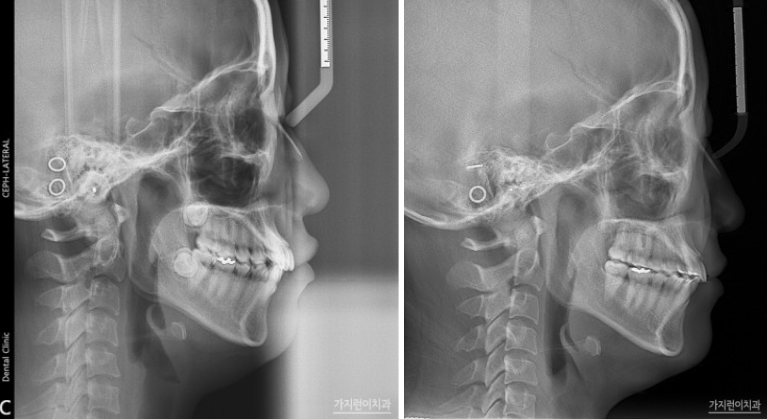

환자분의 경우 거미스마일교정과 더불어 치아의 비뚤어짐, 돌출입 개선을 원하셨습니다. 또 가급적이면 비발치로 진행해보고 싶어하셨는데요. X-ray 진단 결과, 돌출입 증상 자체는 그렇게 심한 편이 아니었습니다. 하지만 돌출감이 느껴지기는 하기 때문에 미니스크류를 이용하여 상하악 치열을 후방 이동시키는 방법으로 진행해봤습니다.

이렇게 진행한 교정은 과연 얼마나 걸렸을까요? 교정은 22년 8월에 시작하여 20개월 후인 24년 4월에 마무리되었습니다. 거미스마일교정이 말끔히 개선된 것을 확인할 수 있었는데요. 상하악 치열이 후방으로 이동했다는 것을 알 수있습니다. 환자가 원하는 개선 부위를 환자의 니즈에 맞춰 개선했기 때문에 만족도도 매우 높았는데요.